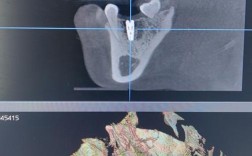

种牙CT片是种植牙手术前不可或缺的检查手段,其质量直接影响种植方案的设计、手术的安全性和远期效果,为确保CT片能全面反映患者的口腔状况,满足临床需求,需从设备类型、扫描参数、图像质量、患者准备等多个方面提出具体要求,设备类型的选择种牙CT检...